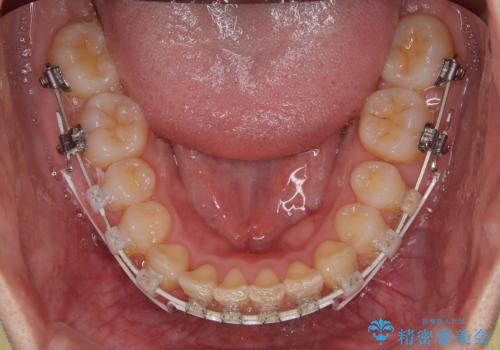

咬合力が強いことと、マウスピースを長時間装着する自信がないとのことで、ワイヤー装置にて矯正治療を行うこととしました。

下顎臼歯を起き上がらせるためにユーティリティーアーチを使用し、一気に深い咬み合わせを改善することができました。